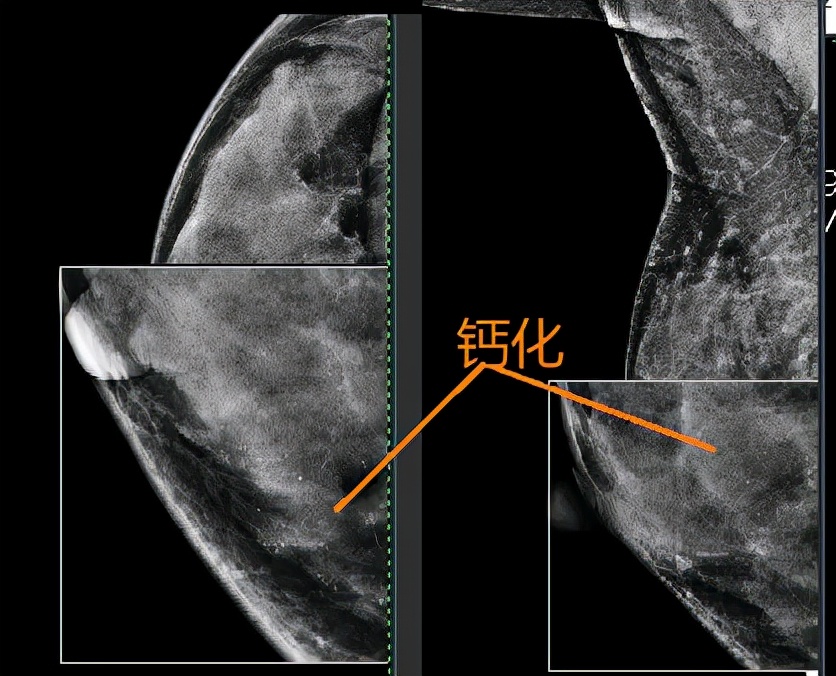

1月上旬,一位B超提示“右乳Birads3类”、钼靶提示“右乳内下象限区域分布细小多形性及模糊不成形钙化,Birads4a"、乳腺增强MR报告”右乳内侧份线样强化,BI-RADS 3类“的患者来我门诊咨询。

钼靶发现右乳内下象限钙化